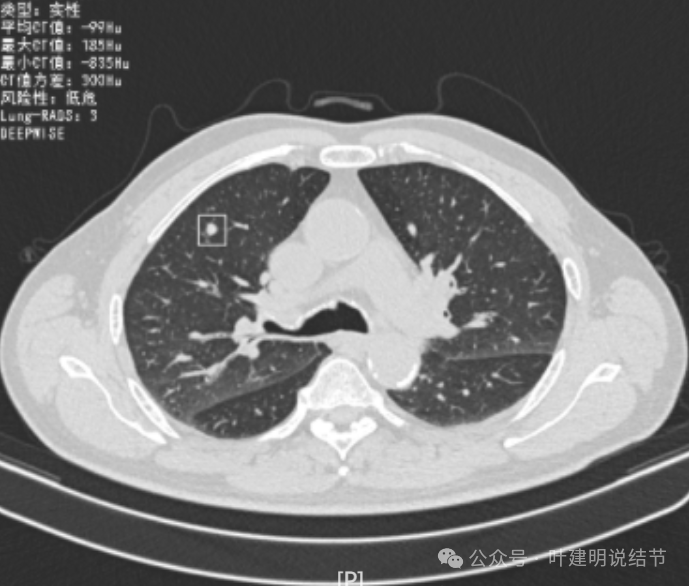

这是冠状位、矢状位与轴位的影像。

增强纵隔窗见病灶内部的密度好像低于周围区域,像坏死。

邻近胸膜无牵拉,灶内有低密度区,局部有点状液性密度。邻近胸膜较为广泛的增厚或胸膜反应。

病灶与胸膜接触面宽,病灶内部密度较低。